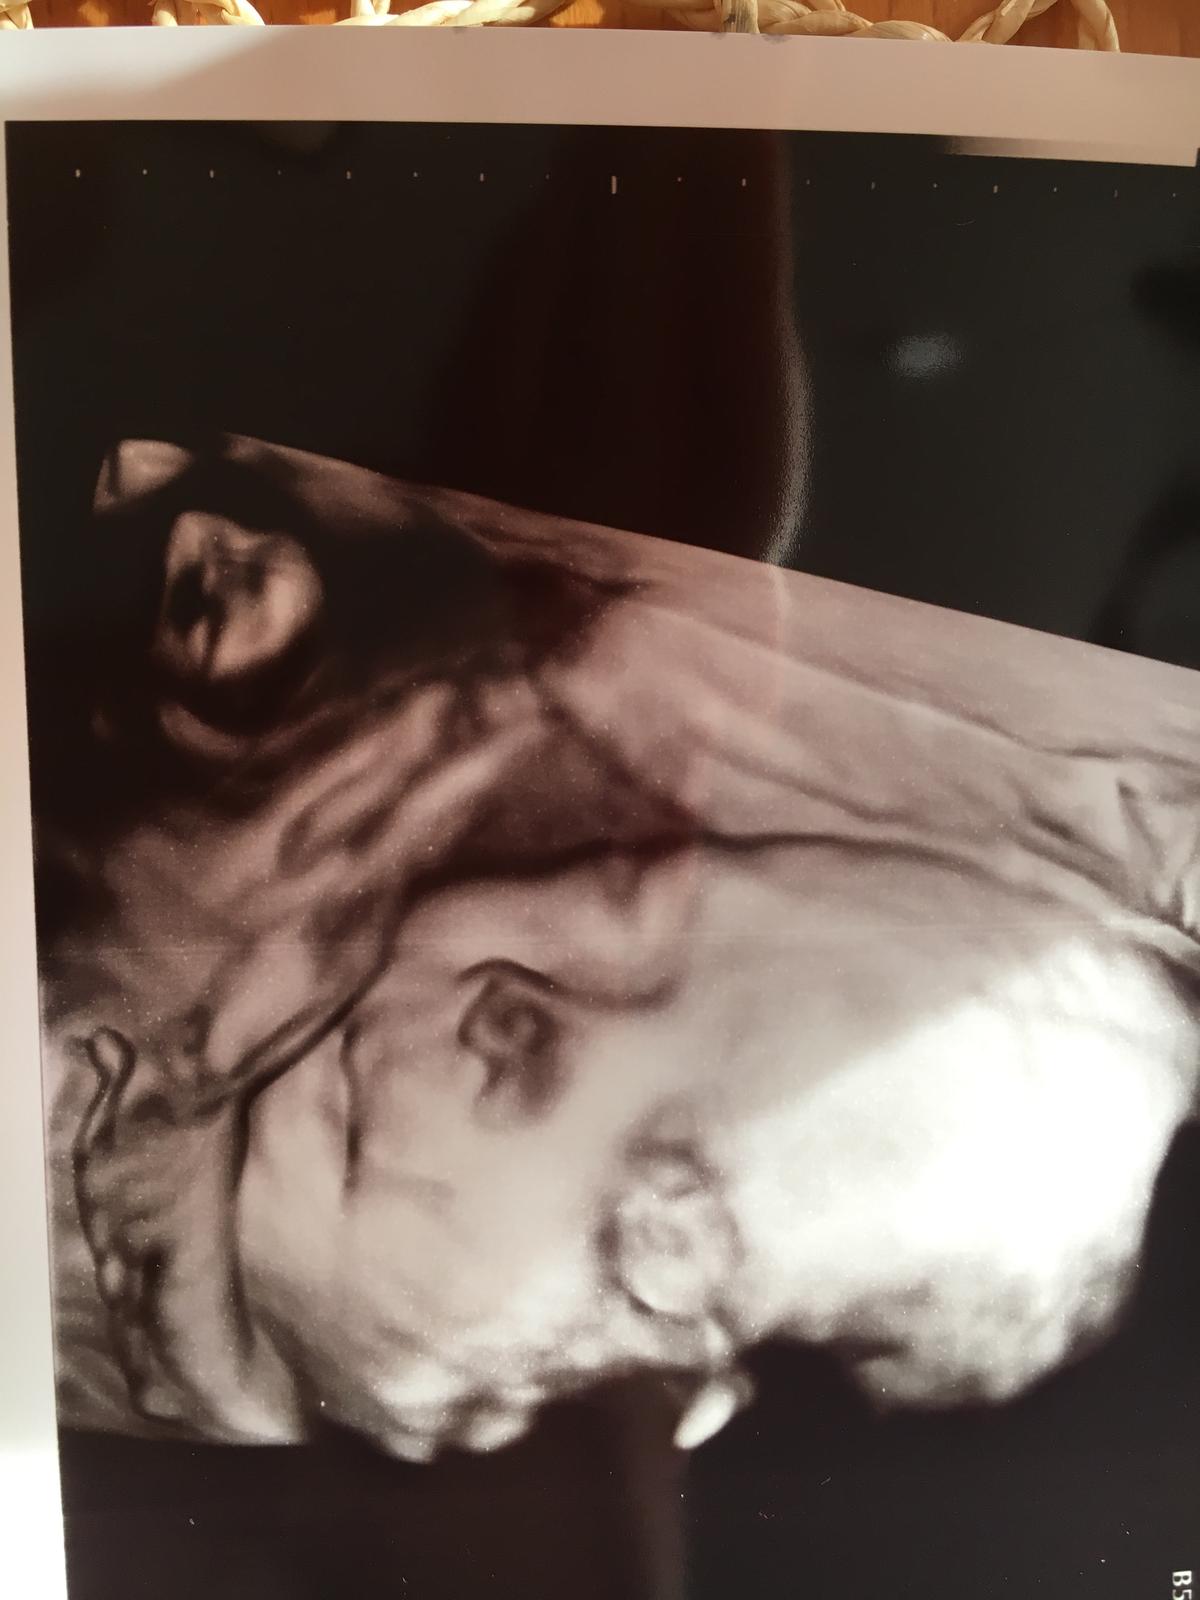

Malička je v poriadku krásne si oblizovala ručičku 👼🏼❤️😂 Váži 1112g .

Lekár nám aj krásne odfotil maličkú tak sa manžel pýta na koho sa podoba 😂 Úplne unesený z malej ❤️👼🏼🙏🍀